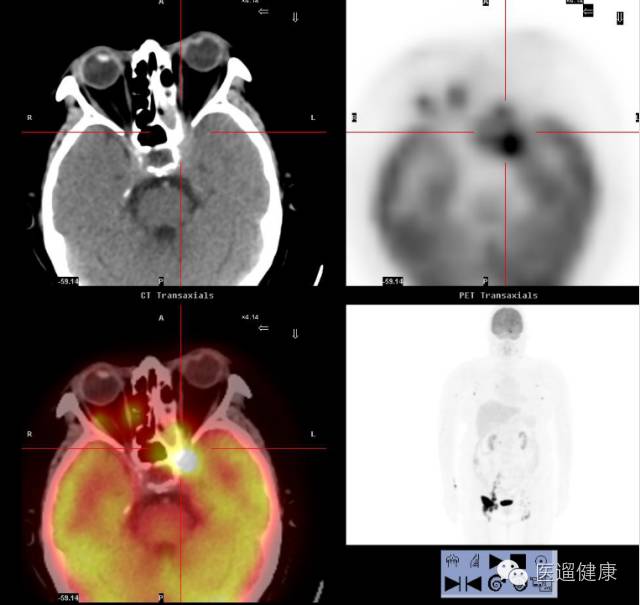

案例三、

PET/CT协助淋巴瘤首次分期病例

病患:女,64岁,左眼疼痛、视力下降一月余。

外院MRI提示左蝶筛窦炎。

左筛窦内窥镜手术,病理:左筛窦NHL(非霍奇金淋巴瘤)(DLBCL)。

入院时初步分期:IA期。

PET/CT显像目的:协助临床准确分期。

↑

分期上调为IIIA期

→

左海绵窦增宽,左视神经孔受压,前床突骨质硬化并边缘骨质侵蚀,SUV最大值约13.2

该病例通过

PET/CT后分期上调为IIIA期